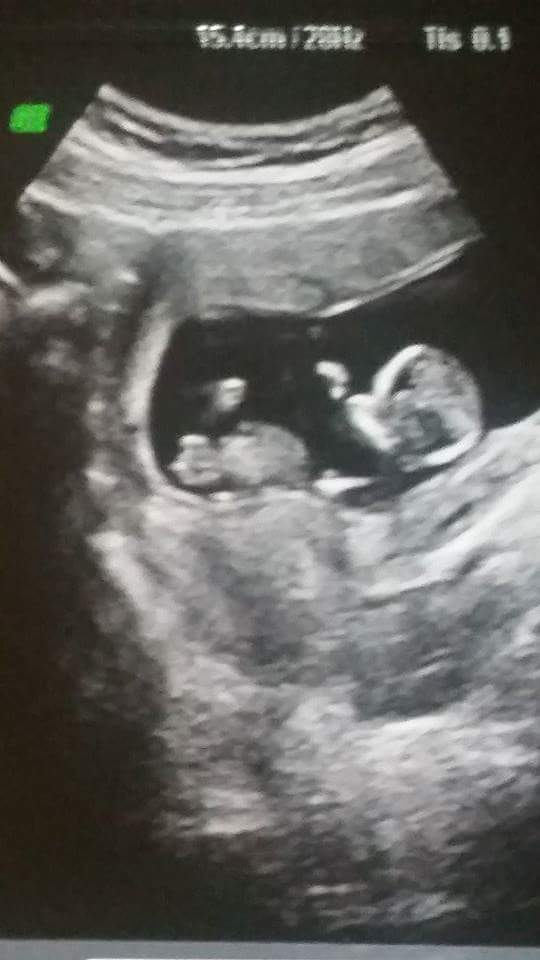

Okay so I messaged the elective ultrasound place and asked for a side nub shot until I receive my disc with all my photos. She sent me the side nub shot and then 2 more potty shots saying there was no way this baby is anything but a girl.

So here's the nub shot. Does it look girly?!